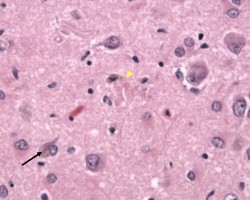

Granulovacuolar degeneration

High power H&E microscope image showing intraneuronal large vacuoles (arrows), each harboring a central granule. Seen with granulovacuolar degeneration of Alzheimer’s disease.